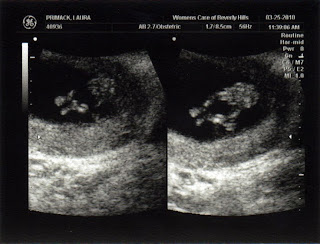

3 Month Ultrasound

James and I visited Dr. Katz's office for our three month ultrasound. The little munchkin was dancing around, showing off its ten fingers and its long legs— just like Daddy (we'll see how long that lasts!)